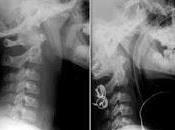

Detectar los Factores de Riesgo Cervical reduce el uso de las Tomografías

El 15 agosto 2019 por Jesus Gutierrez :